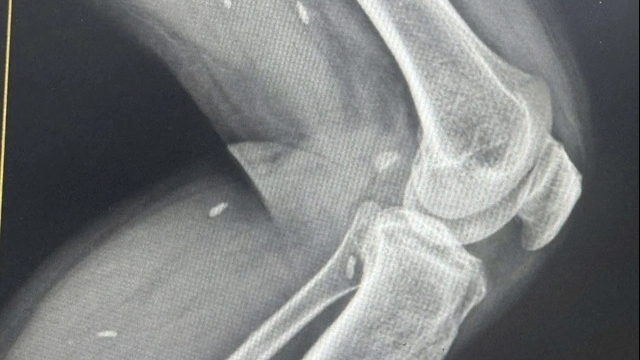

Theo các nhà điều tra, chất Vitamin E acetate thường được tìm thấy trong thực phẩm và được sử dụng trong các mỹ phẩm như kem dưỡng da, song có thể gây tác động đến chức năng của phổi nếu người sử dụng hít phải nó. Trong cuộc họp báo qua điện thoại, Phó Giám đốc phụ trách CDC Anne Schuchat cho biết các phát hiện đều cho thấy chất vitamin E acetate là nguyên nhân hàng đầu dẫn tới sự tổn thương trong phổi của người bệnh.